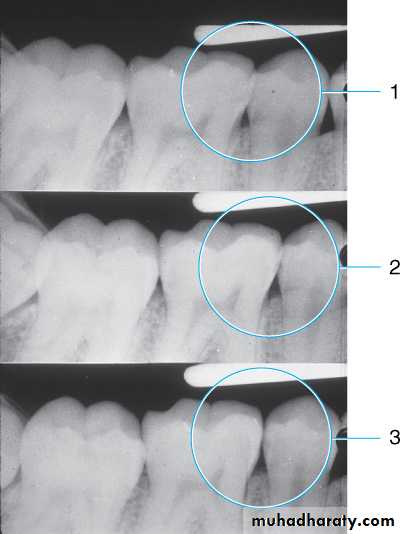

Horizontal angulation. (1) Improper horizontal angulation prevents viewing interproximal caries. (2) Improved horizontal angulation, but caries difficult to view. (3) Proper horizontal angulation shows interproximal caries